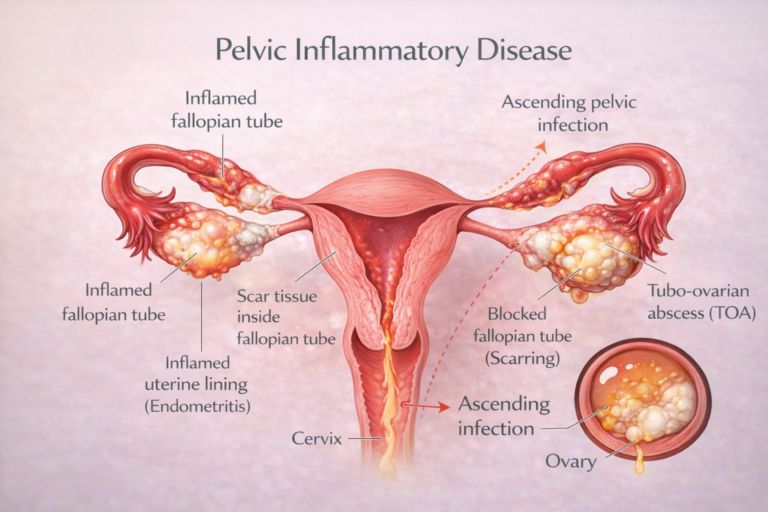

• Permanent scarring of the fallopian tubes (Blocked Tubes) and the uterus (Asherman’s Syndrome)

• Chronic pelvic pain that makes you look older than your age

• Ectopic pregnancy, which can be life-threatening and lead to permanent infertility

PID is an infection and inflammation of the female reproductive organs, including the uterus, fallopian tubes, and ovaries.

Once the infection enters the upper reproductive tract, it begins to burn, scar, and damage delicate reproductive tissues.